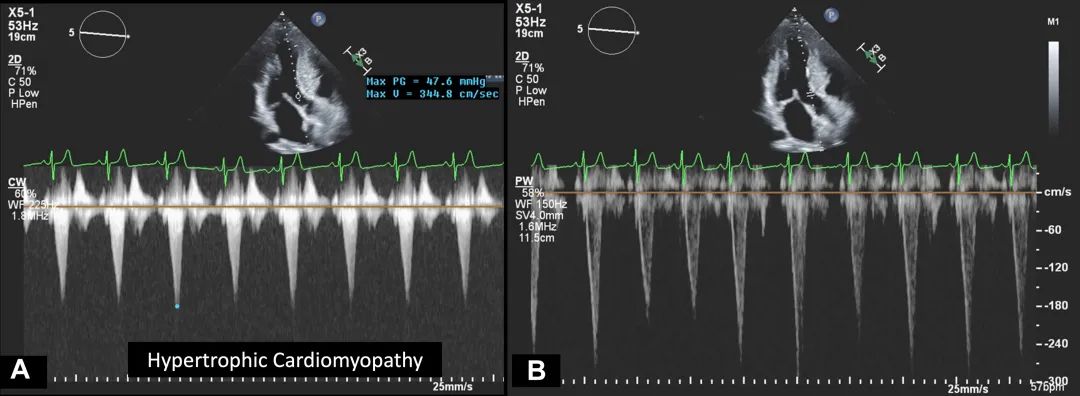

2、务必排除其他导致流出道梗阻的病因,包括瓣下及瓣上狭窄。主动脉瓣下隔膜是一种位于左室流出道的薄膜结构,可能表现为局限性或隧道状。在放大左室流出道图像时,应仔细寻找隔膜并用彩色多普勒检查是否存在位于主动脉瓣下方的左室流出道血流加速现象。这类患者常合并主动脉瓣反流。肥厚型心肌病患者因室间隔肥厚造成左室流出道狭窄。可能伴有二尖瓣前瓣的收缩期前向运动(systolic anterior motion,SAM),由此导致在狭窄部位及室间隔瓣环运动处的彩色多普勒湍流。连续多普勒呈现晚期尖峰的匕首状波形(图17)。在这些患者中,脉冲多普勒取样容积的放置极其重要,需仔细调整取样位置以避免因瓣下梗阻导致的血流加速(多普勒混叠)。

图17. 肥厚型心肌病患者的多普勒波形

肥厚型心肌病患者的连续多普勒波形呈晚期尖峰的匕首状波形(A);脉冲多普勒波形则表现为流速增高并伴有混叠B)。